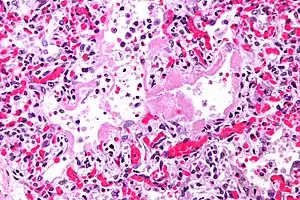

Micrograph of diffuse alveolar damage, the histologic correlate of acute interstitial pneumonitis. H&E stain.

Rapid progression from initial symptoms to respiratory failure is a key feature. An X-ray that shows ARDS is necessary for diagnosis (fluid in the small air sacs (alveoli) in both lungs). In addition, a biopsy of the lung that shows organizing diffuse alveolar damage is required for diagnosis. This type of alveolar damage can be attributed to nonconcentrated and nonlocalized alveoli damage, marked alveolar septal edema with inflammatory cell infiltration, fibroblast proliferation, occasional hyaline membranes, and thickening of the alveolar walls. The septa are lined with atypical, hyperplastic type II pneumocytes, thus leading to the collapse of airspaces. Other diagnostic tests are useful in excluding other similar conditions, but history, X-ray, and biopsy are essential. These other tests may include basic blood work, blood cultures, and bronchoalveolar lavage. The clinical picture is similar to ARDS, but AIP differs from ARDS in that the cause for AIP is not known.